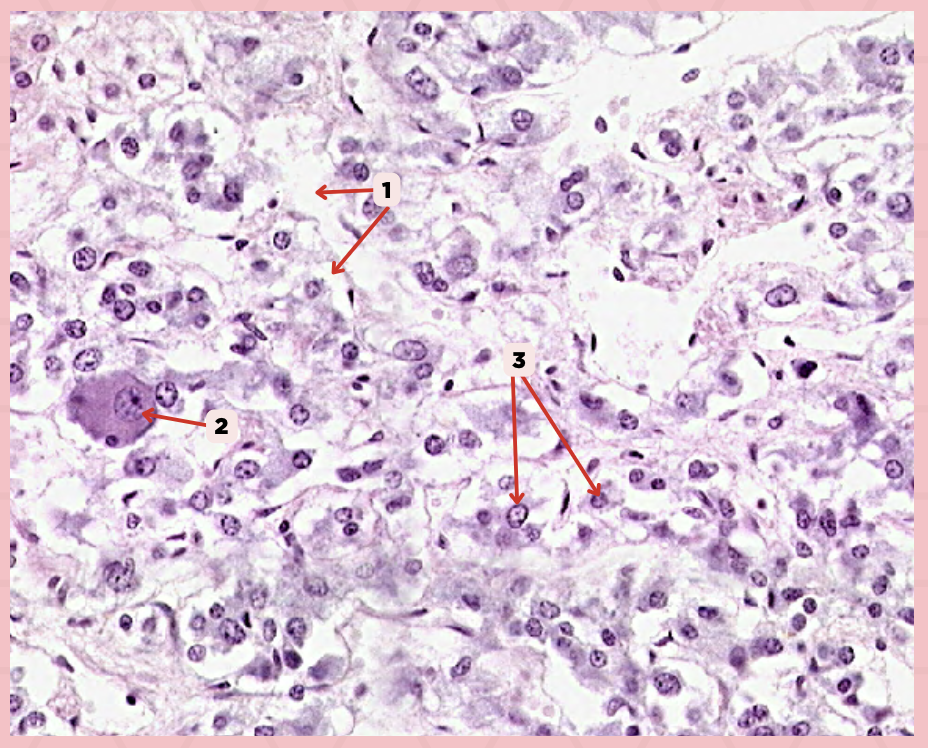

Pancreas

Identify the specimen.

Islets of Langerhans

Identify the structure labeled as 1.

Pancreatic Acini

Identify the structure labeled as 2.

Reticular Tissue

Identify the structure labeled as 3.

Beta-cells

Which cells occupy the central area of #1?

Pancreatic Acini

#3 delineates the pale- staining cells from the darker-staining cells. What do you call the darker-staining cells?